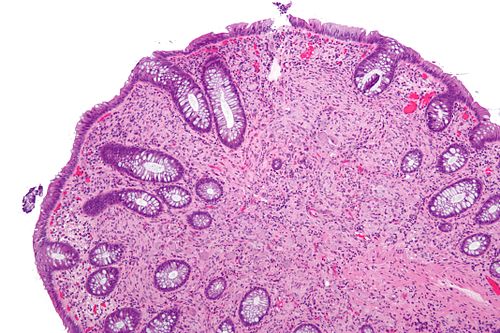

52 year old man, polyp.

Colon.

High magnification. H&E stain.

There are large cells in the stroma. The cells have a prominent nucleolus!

NSE Large round cells POSITIVE

S-100Spindle cells POSITIVE

Synaptophysin Large round cells POSITIVE

Ganglioneuroma.